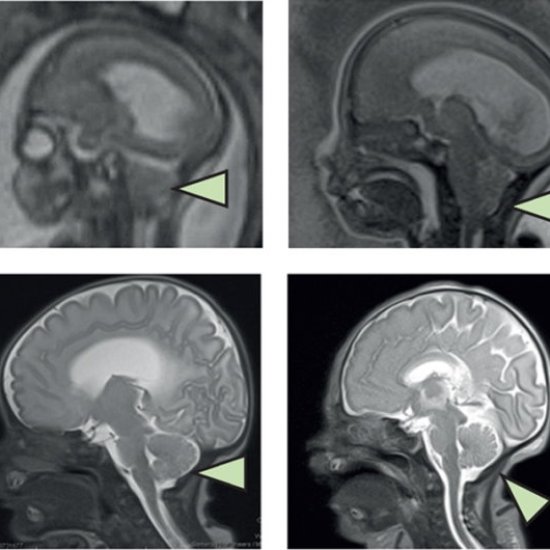

Classifying pediatric brain tumors with liquid biopsy and AI

Clues in the CSF: Researchers have developed the first high-precision method that can theoretically diagnose common brain tumors in children and adolescents without surgery.